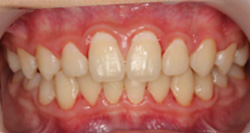

6、過蓋咬合(噛み合わせが深い)

・混合歯列期からからの治療を推奨します。

成長期のお子さんで、骨の大きさに問題があるために噛み合わせが深くなってしまっている場合、成長期の初期段階で治療を始め、上下の顎の成長を適切に管理していくことが好ましいとされています。

骨格的な問題の場合は、治療が遅れてしまうと後で大きな手術が必要になってしまうというリスクがありますので、まずはお子さまの不正咬合がどのような問題から引き起こされているのか、正しい診断を受けることが大切です。

また過蓋咬合の場合は、噛み合わせが深いために前方や側方への顎機能運動にも障害が生じてしまいます。

将来の顎関節や筋機能への影響などという面から見ても、まずは早めに相談されることをおススメします。